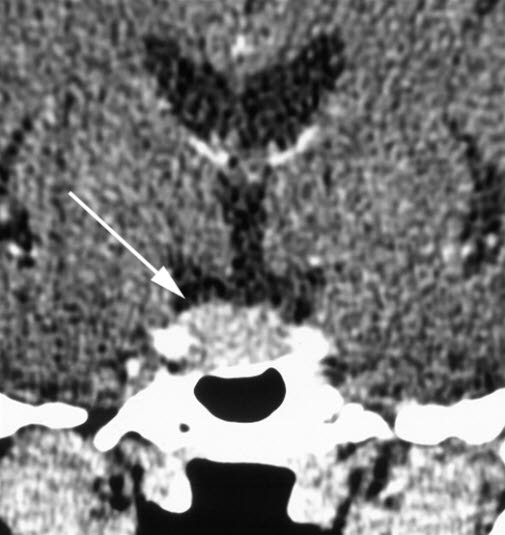

Coronalt snitt gjennom hypofysen etter intravenøs kontrastinjeksjon. Hypofysen (pil) er generelt forstørret, med konvekst bukende konturer.